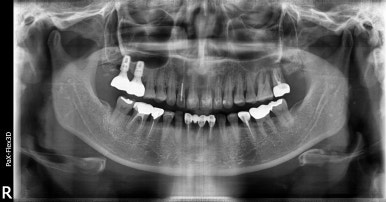

오른쪽 (실제로 왼쪽) 상악 앞니 임플란트 치료 전

2023-01-09

저희 디데이치과에서 치료를 받으신 환자분은 사진상 오른쪽(실제 왼쪽) 앞니 2개(#22, 23) 치아가 불편하신 상태였는데요.

잇몸뼈가 많이 내려앉아있고, 이대로는 더이상 치아를 사용하기 어려울 것으로 판단되어

발치 당일에 임플란트를 식립하면서 뼈이식까지 진행하고, 3개월 후 경과를 보고 보철까지 진행하는 스케줄로 계획해드렸습니다.

통상 상악 앞니같은 경우에는 뼈가 얇고 하악에 비해 무르기 때문에 임플란트 식립부터 보철까지

기간이 4~6개월 이상 걸린다고 생각해주시면 됩니다. 뼈이식이 추가될 경우 더 오래 걸릴 수 있고요.

오른쪽 위(실제로는 왼쪽) 앞니 임플란트 전후 비교

(전) 2023-01-09 (후) 2023-08-18

이 환자분 역시 최초 수술부터 임플란트 보철물 완전 부착까지 약 7개월 정도 소요되었습니다.